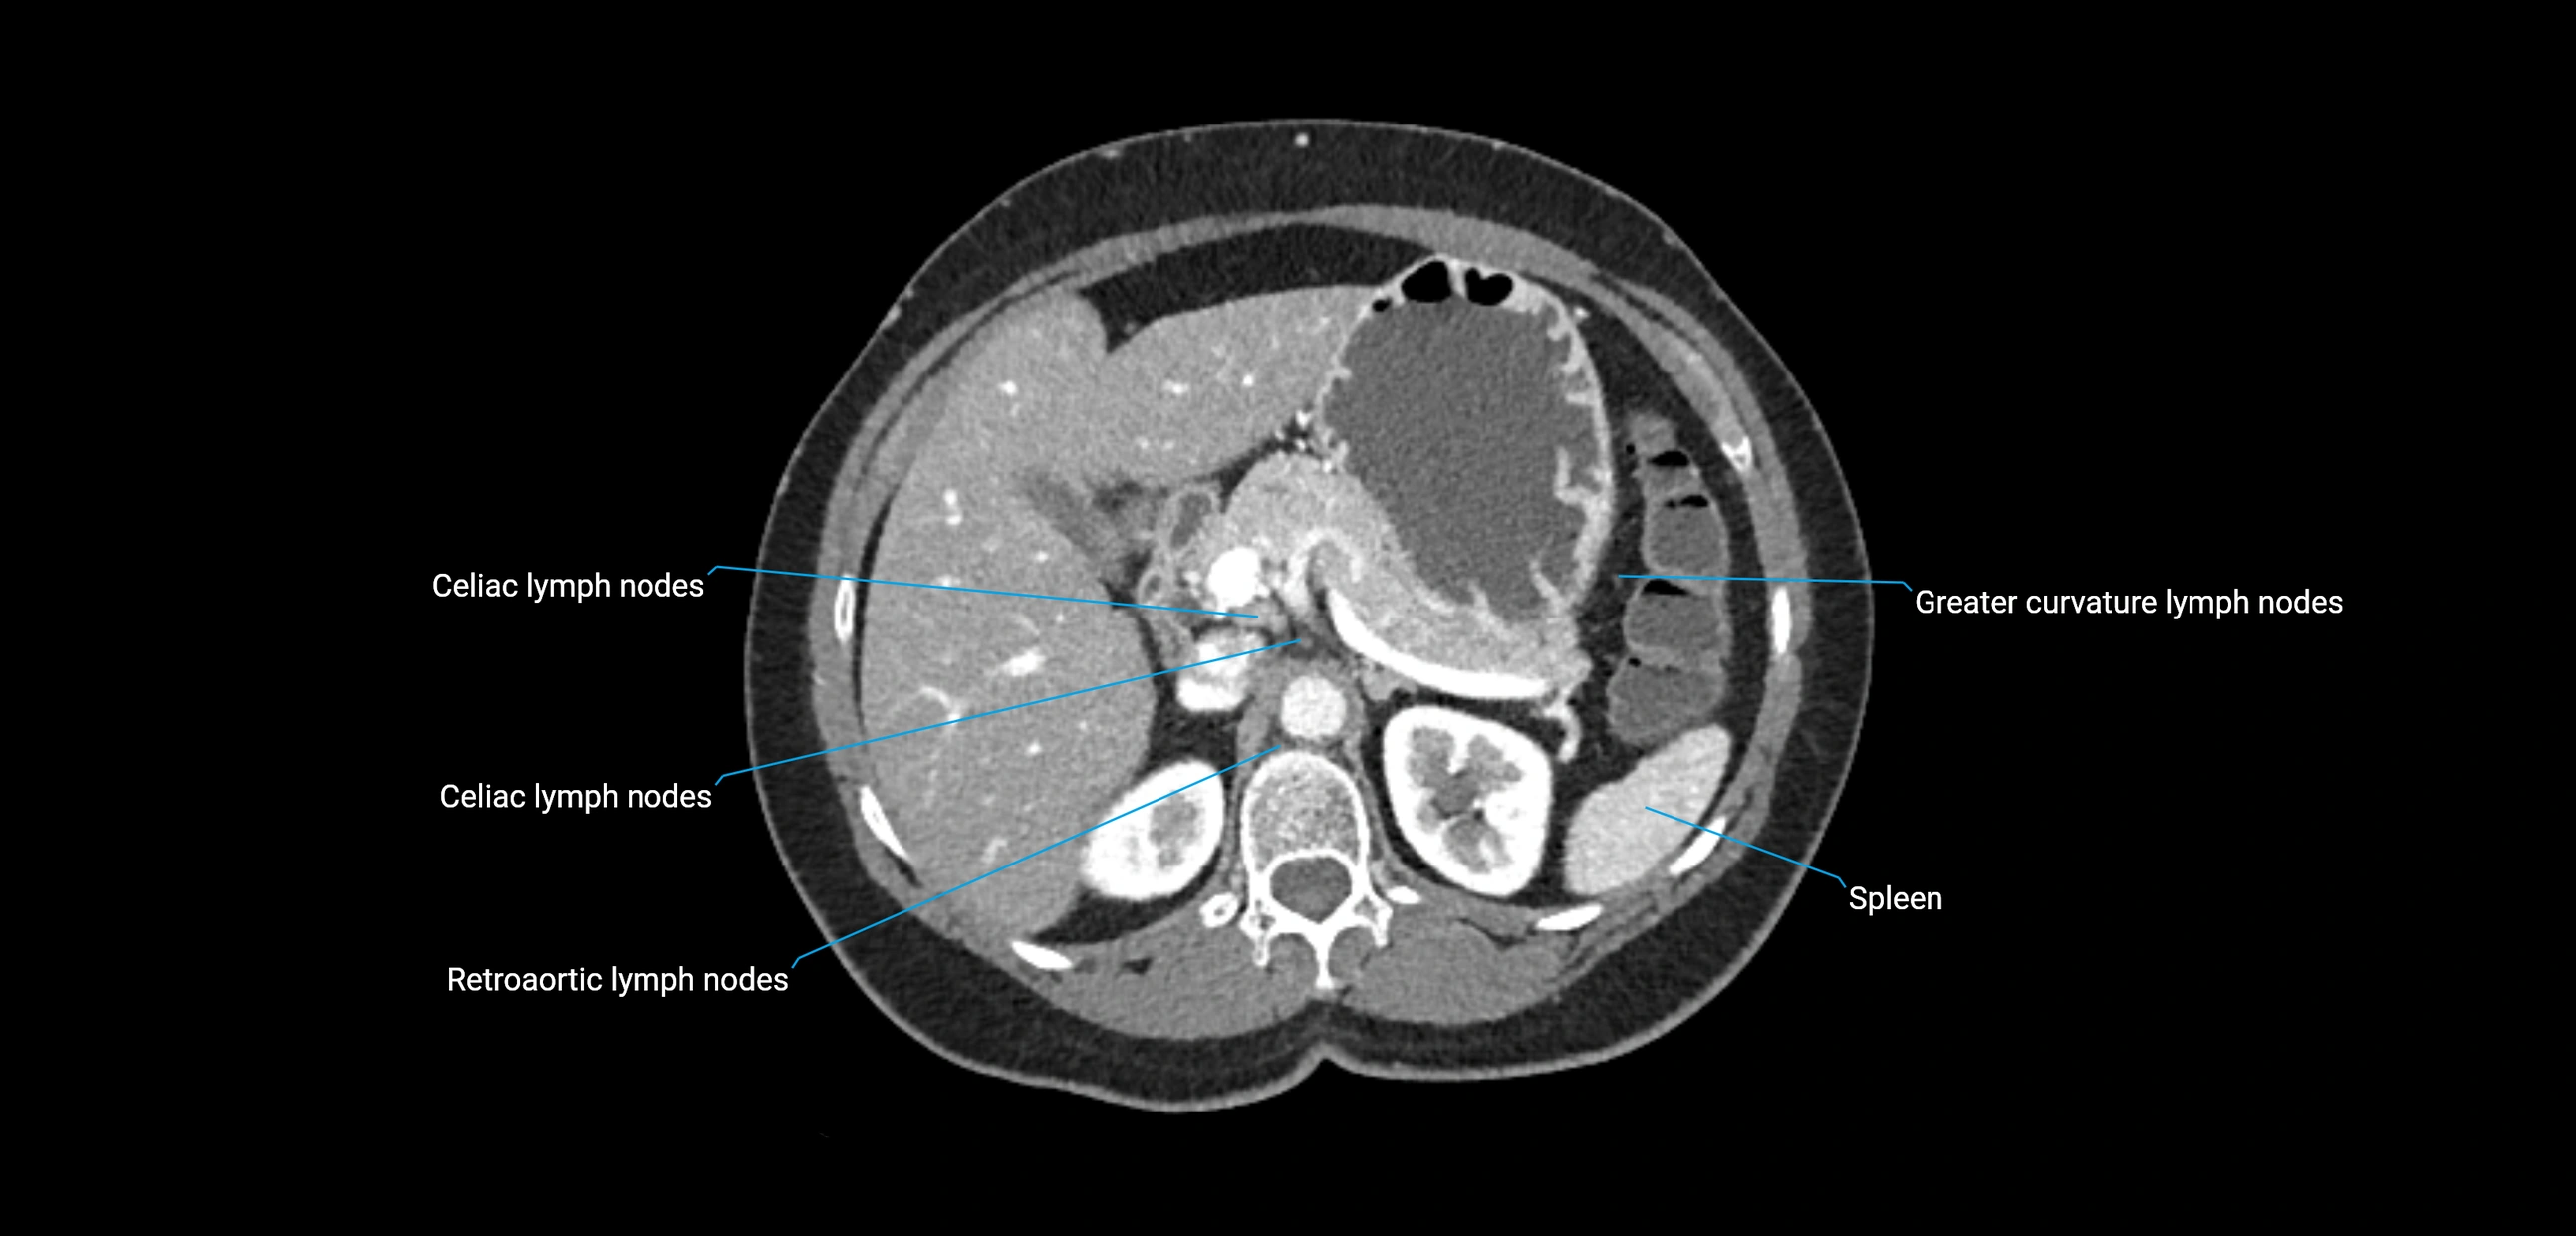

CT Appearance

CT Pre-Contrast:

• Nodes appear as soft-tissue density nodules adjacent to the aorta and IVC

• Calcification may be seen in chronic infections (e.g., tuberculosis)

CT Post-Contrast:

• Normal nodes enhance homogeneously

• Malignant nodes may show heterogeneous enhancement, central necrosis, or conglomerate formation

• Size >1 cm short axis is suspicious, though morphology and distribution are equally important

CT Venography (CTV):

• Demonstrates nodal encasement or compression of adjacent vessels (aorta, IVC, renal veins)

• Useful in staging testicular and ovarian malignancies

• Provides 3D reconstructions for retroperitoneal lymph node dissection planning